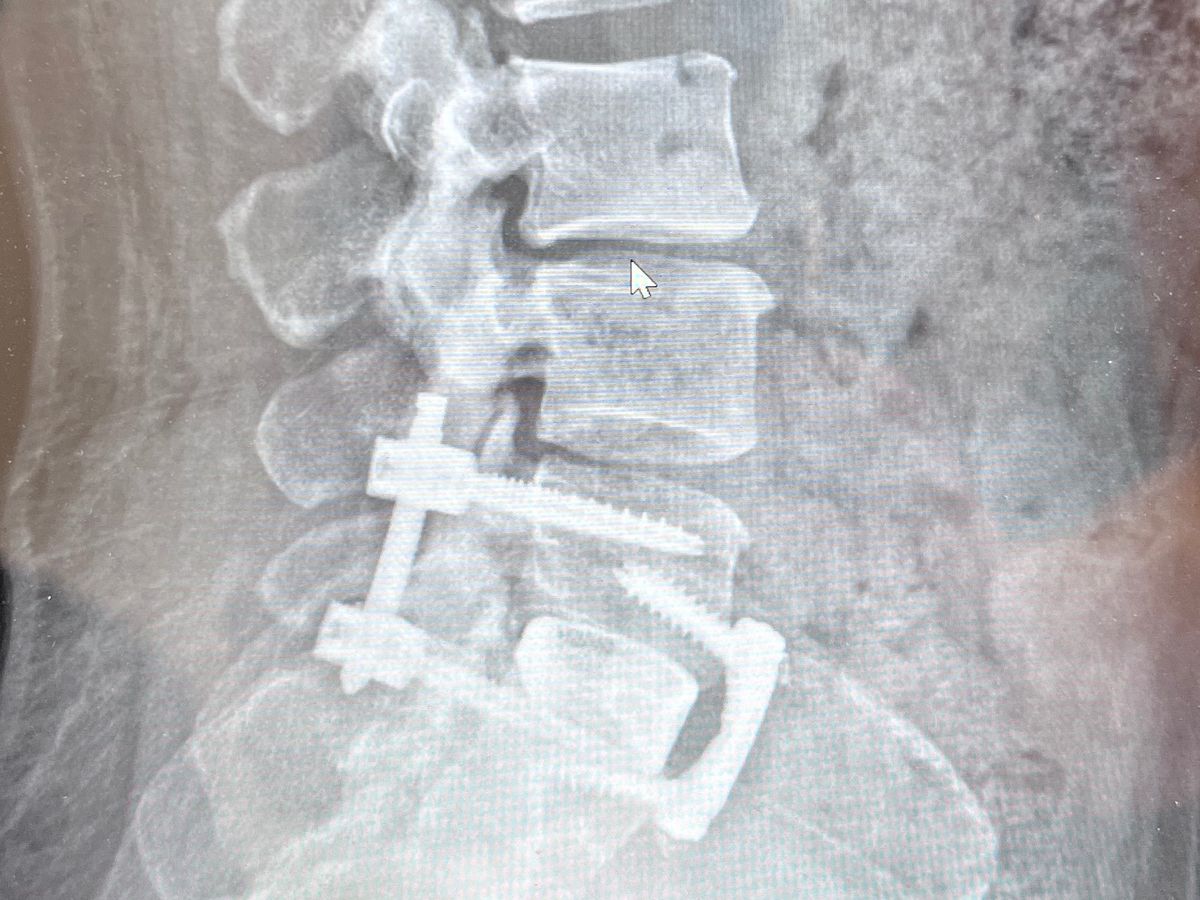

I’m going under one more spine surgery on October 17th for a L5-S1 fusion.

During the year of 2023 I worked hard to get well and trying to avoid this last surgery but unfortunately at this point the degeneration is too advanced and there isn’t any other option besides surgery.